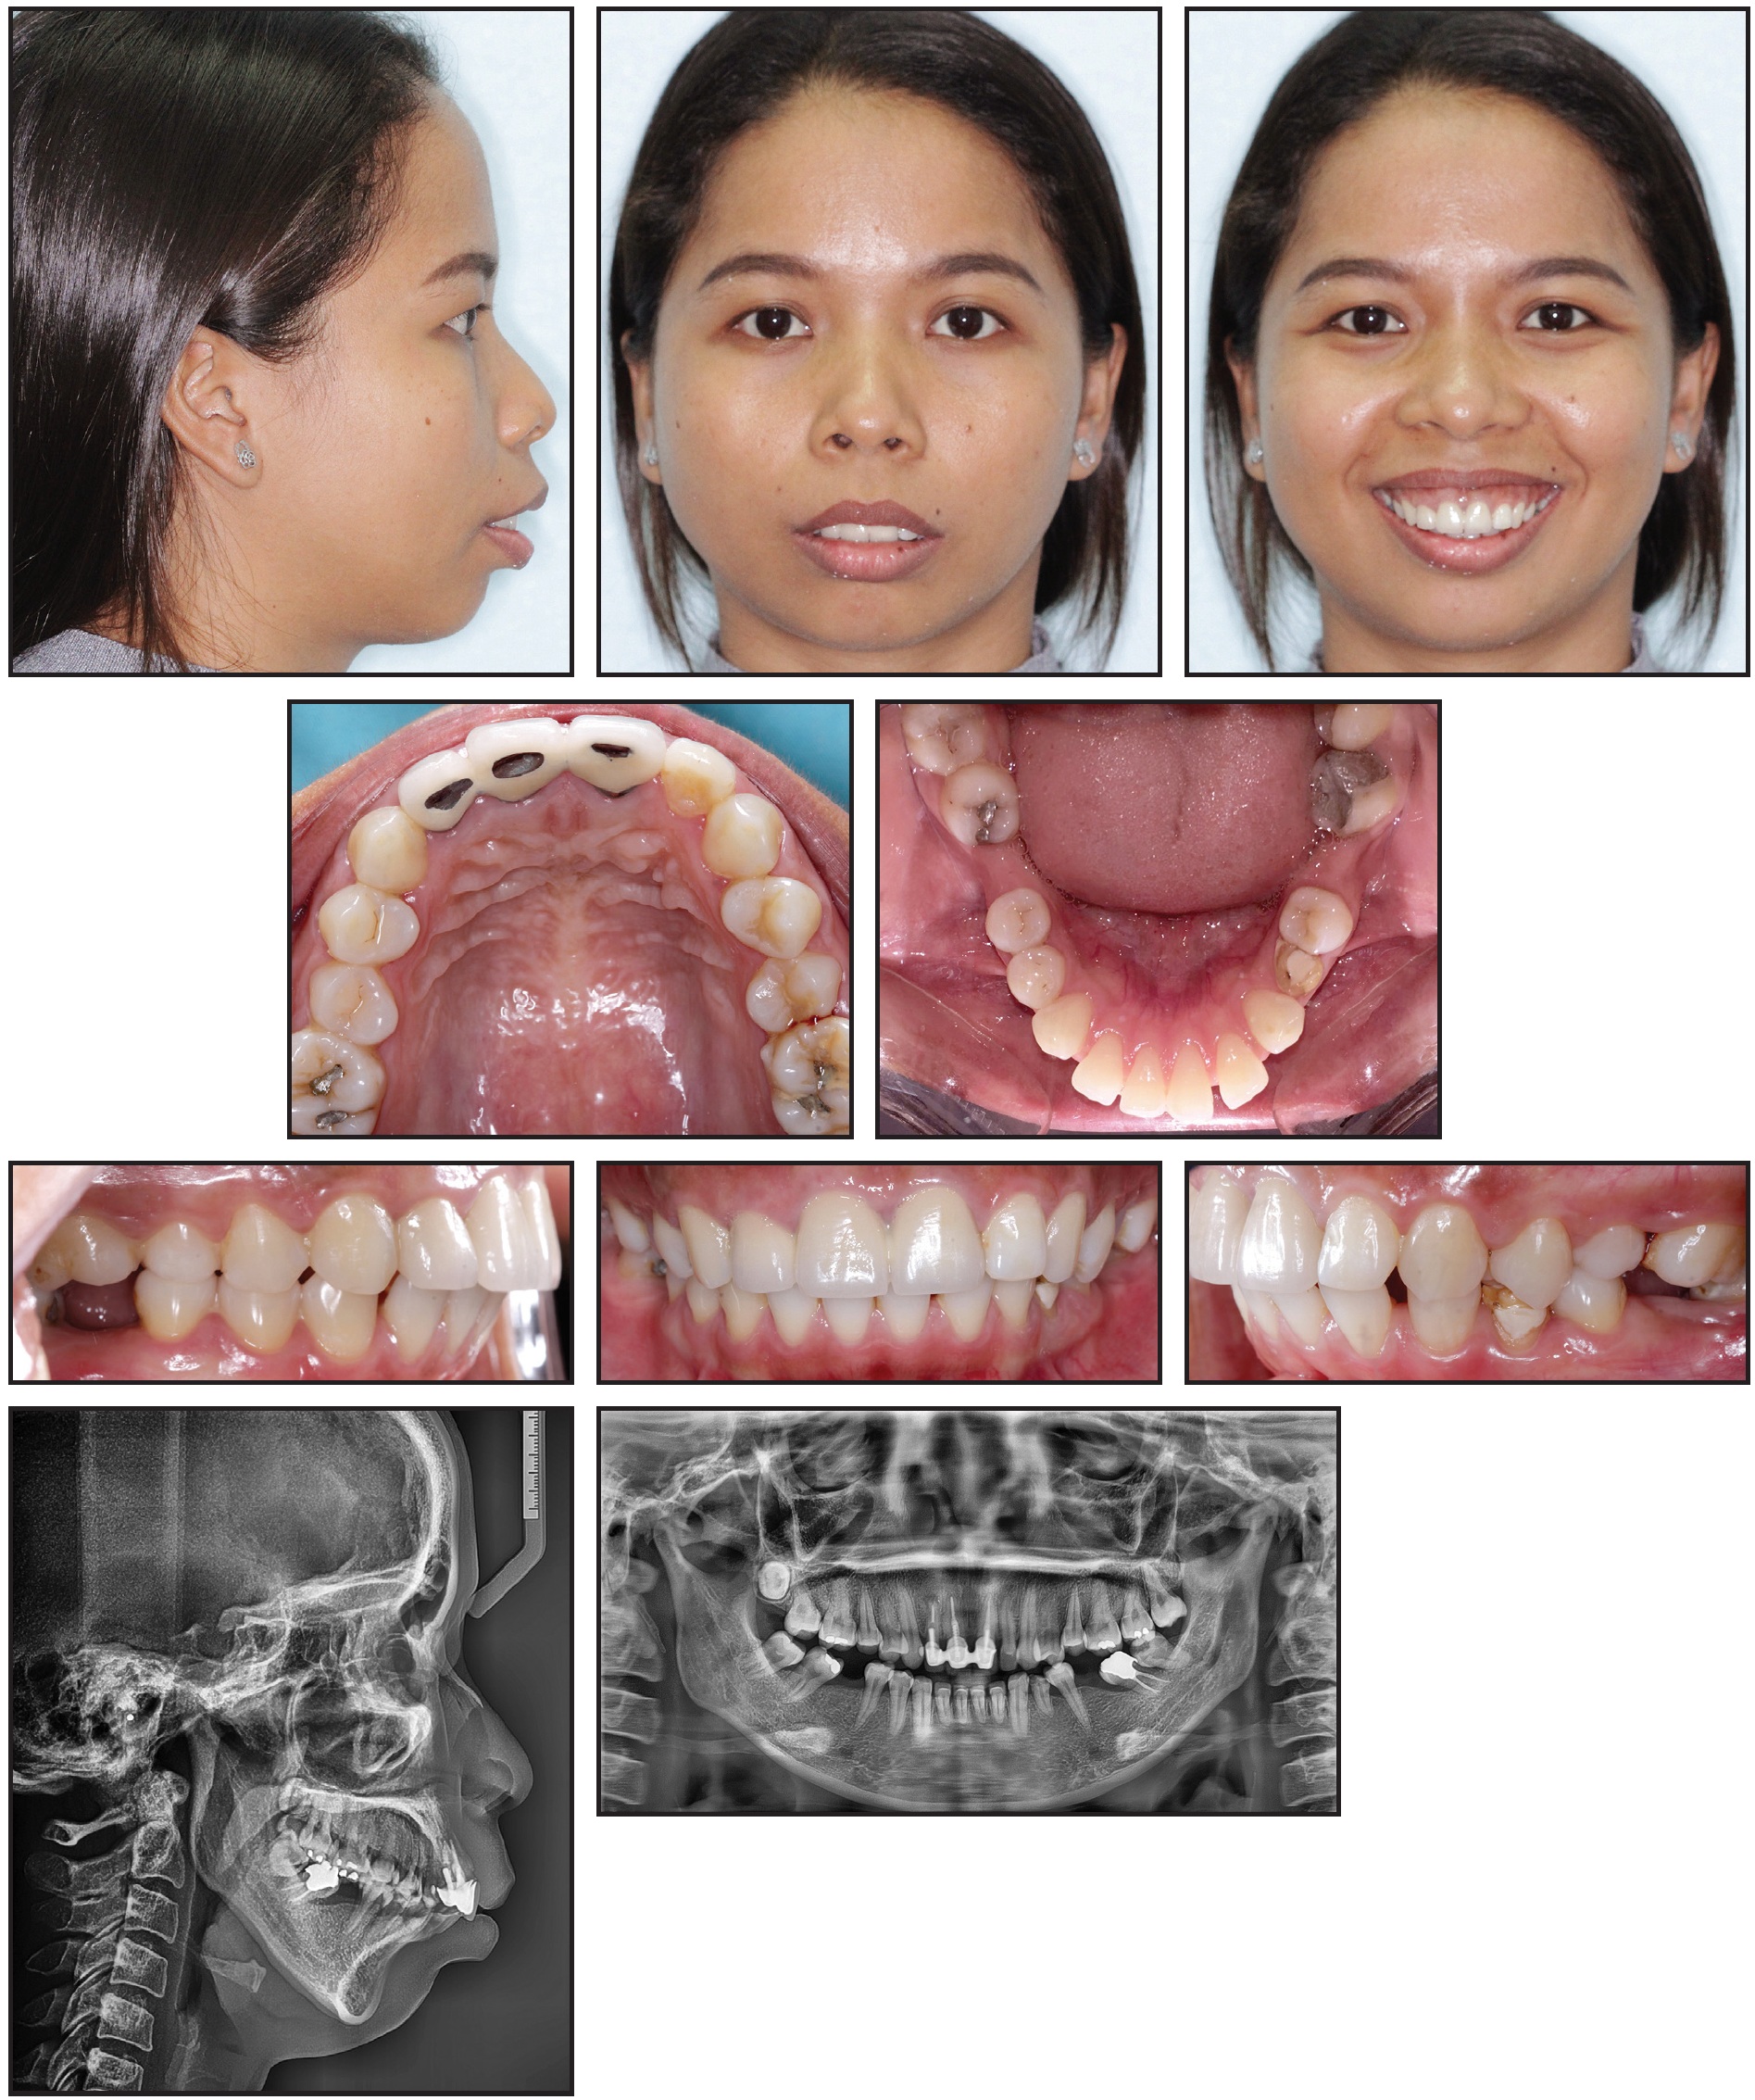

A 14-year-old female presented with the chief complaint of an unpleasant smile with crooked anterior teeth (Fig. 1). The patient exhibited a triangular face with a mildly excessive lower third and a slight deviation of the nose to the right. The facial profile was straight, and the nasolabial angle was slightly open. Incisor exposure in smiling was acceptable, but there were wide lateral black corridors. The maxillary dental midline was deviated 1mm to the right with respect to the mandibular dental midline, but the latter was coincident with the facial midline in smiling. The patient showed a slight bilateral Class III molar relationship (–1.5mm) and a bilateral Class I canine relationship, with a lateral open bite on both sides. The overbite was reduced (.4mm), but the overjet was normal (1mm). Transversely, the patient had a maxillary deficiency, with a V-shaped upper arch and a unilateral crossbite between the upper right first and second premolars. The upper incisors were tipped toward the upper right canine, which was ectopic and high in the vestibule, contributing to a cant of the maxillary occlusal plane. The upper arch was severely crowded, but the lower arch was only mildly crowded, with excessive curves of Spee and Wilson.

Fig. 1 14-year-old female patient with skeletal Class III malocclusion, lateral open bite, ectopic upper right canine, canted maxillary plane, severe crowding in upper arch, and secondary atypical swallowing before treatment.

Functional tests found secondary atypical swallowing, with tongue interposition between the arches and constriction of the perioral mimic muscles, especially the orbicular muscle.

A panoramic radiograph revealed the presence of all teeth except for the upper third molars, with no signs of apical resorption or interdental bone defects. Cephalometric analysis (Table 1) indicated a skeletal Class III relationship (ANB = –2°, Wits appraisal = –5.3mm), with the maxilla in a retrusive position (SNA = 76.8°, A-Na perp = –3.8mm). The facial pattern was normodivergent (FMA = 27.4°), although a general tendency toward a hyperdivergent pattern could be seen (MP-SN = 36.3°). The upper incisors were normally inclined, with a slight tendency toward proclination (U1-PP = 112.2°), while the lower incisors were retroclined (IMPA = 84°).